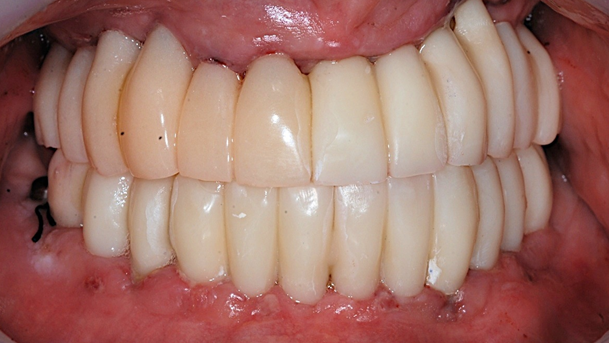

Clinical case: Preview the final goal first, make the ideal treatment plan, then realize it using the appropriate tools

- Courtesy of Dr. Sang Tack Lee, Korea -

Dr. Sang Tack Lee, edentulous, digital full mouth prosthetics, digital guided surgery, #11, #13, #14, #16, #17, #21, #23, #24, #26, #27, #33, #34, #36, #37, #43, #44, #46, #47, guided surgery, flapless, AnyRidge, R2GATE, Mega ISQ, MEG Torq, MEG Engine, R2GATE Full surgical kit

AnyRidge implant system, R2GATE Guide, R2GATE full surgical kit , Mega ISQ